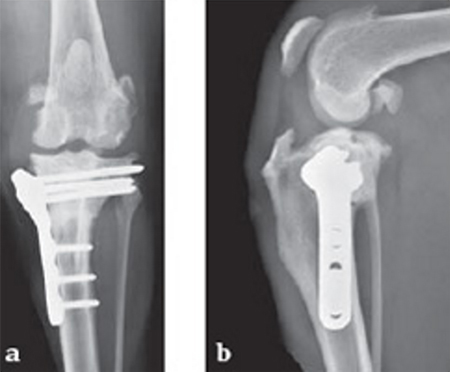

A four-year-old, female, spayed, 33 kg English bulldog had a CrCL tear and a medial patellar luxation. The small stature 3.5 mm TPLO plate was perfect for this dog due to the small profile of the bone and the need to use a heavier plate (3.5 vs a 2.7 mm). In the past, veterinary surgeons have been forced to either squeeze the standard TPLO 3.5 mm plate on the bone or use an undersized TPLO 2.7 mm plate. In this patient, the shorter and smaller profile head of the small stature TPLO 3.5 mm was perfect.